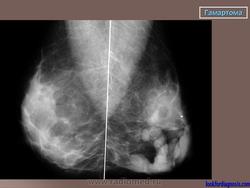

Гамартомы молочных желез.

Приложения: